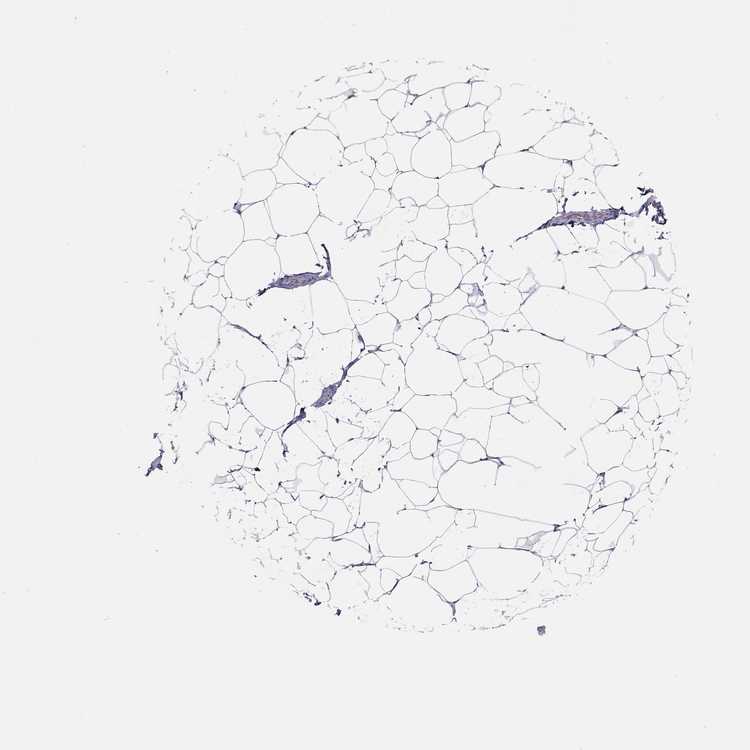

BREAST - Antibody stainingi

Antibody staining in the annotated cell types in the current human tissue is reported as not detected, low, medium, or high, based on conventional immunohistochemistry profiling in selected tissues. This score is based on the combination of the staining intensity and fraction of stained cells.

Each image is clickable and will lead to virtual microscopy that enables deeper exploration of all samples and also displays staining intensity scores, fraction scores and subcellular localization as well as patient and tissue information for each sample.

Antibody HPA061693

Adipocytes Not detected

Glandular cells Not detected

Myoepithelial cells Not detected